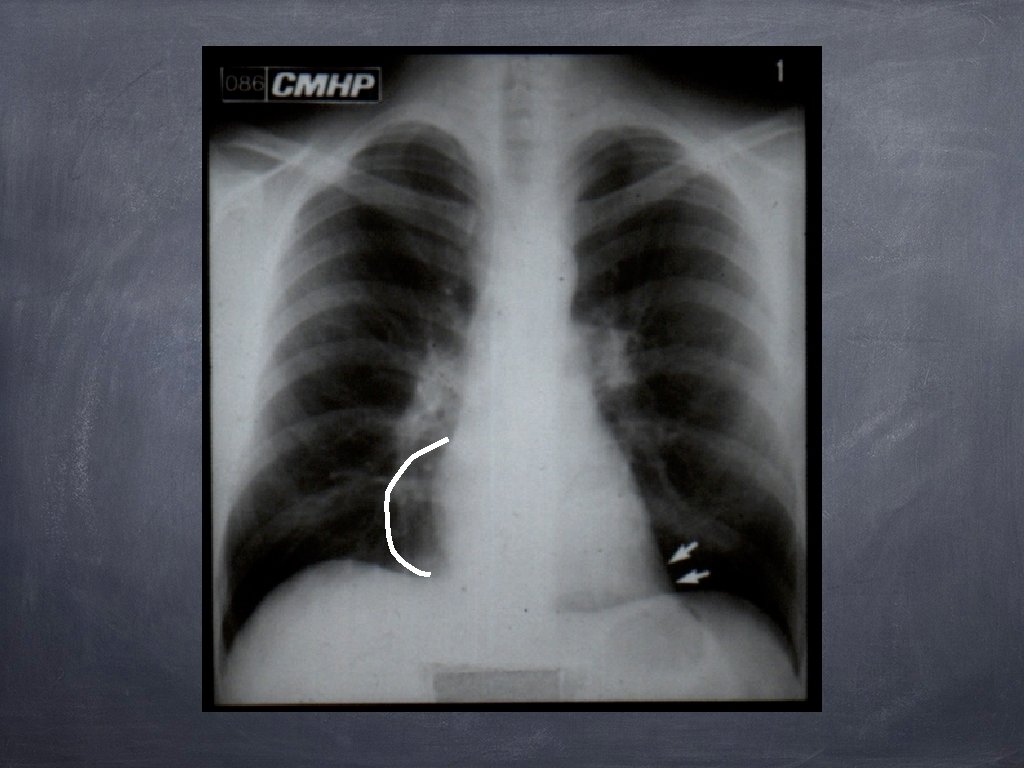

Hipertensiunea arterială pulmonară 1. Hiluri pulmonare cu arie de proiecție crescută, ramificate 2. Decalibrare bruscă a ramurilor de AP în regiunea perihilară; 3. Periferie pulmonară „săracă“ în benzi de desen pulmonar.

Dilataţia AS Incidenţa de față: Bombare AMS in porțiunea inferioară; Deschiderea unghiului carinei; Arc suplimentar pe marginea dreaptă a cordului